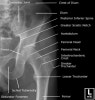

- Hip AP view

1) Alignment and Bones

① 내측 대퇴골의 아래에서 시작하여 목과 머리를 지나 돌기까지 근위부 대퇴뼈의 바깥면을 따라서 끊어진 것이 있는지 조사합니다.

④ 절구 관절면, 앞 뒤 가지의 피질선(cortical line)을 체크합니다.

⑤ 양측 볼기뼈는 좌우 대칭으로 보여야 합니다.

Hip dysplasia

Centre-edge(CE) Angle

Acetabular index

Proximal femur morphology